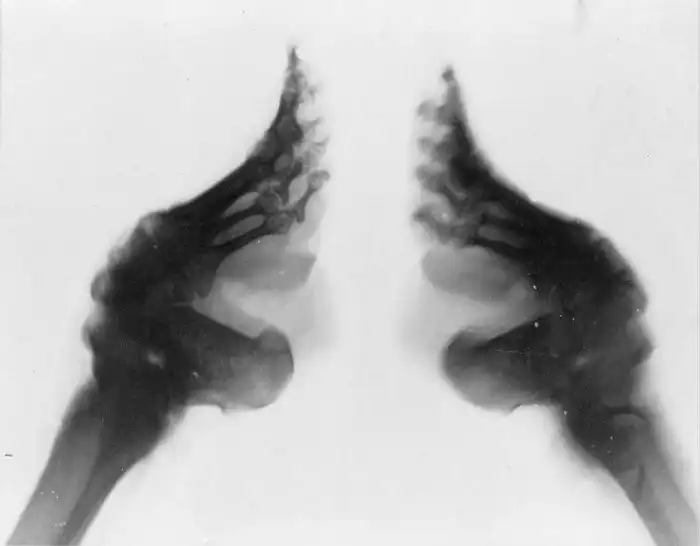

Идеальная нога не должна была превышать 7 сантиметров в длину — именно такие ноги назывались «золотыми лотосами».

Сначала девочкам подрезали ногти, чтобы предотвратить их врастание, обрабатывали ступни настоями трав и квасцами. Затем брали ткань метра 3 в длину и 5 см в ширину, подгибали все пальцы, кроме большого, и перебинтовали ноги таким образом, чтобы пальцы стремились к пятке, а между ними и пяткой образовывалась арка.

Конечной, самой большой опасностью была инфекция ног. Хотя ногти девочкам постригали, они все равно врастали, это приводило к воспалению. В результате временами возникал некроз тканей. Если инфекция перекидывалась на кости, пальцы отпадали — это считалось хорошим знаком, потому что позволяло забинтовать ноги еще туже. Значит, ступня уменьшится и приблизится к заветным 7 сантиметрам.